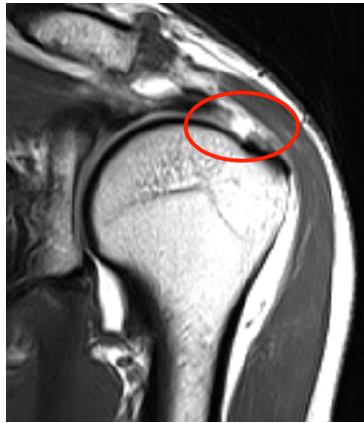

영상 진단 검사

MRI: 회전근개의 손상 정도를 정확하게 파악할 수 있으며, 힘줄의 파열 및 근육의 상태를 세밀하게 확인할 수 있습니다.